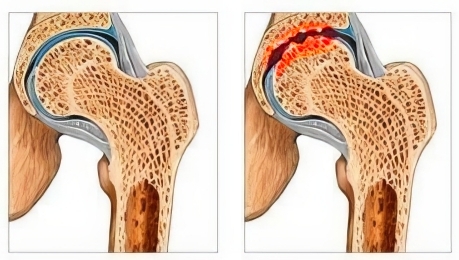

Dažniausia senėjimo priežastis žmonėms vyresniems nei 50 metų yra DEGENERACINĖS SĄNARIŲ LIGOS — vadinamasis sąnarių nusidėvėjimas. Dauguma žmonių ignoruoja šią problemą, tačiau laikui bėgant tai ne tik sukelia diskomfortą, bet ir veda prie negrįžtamo kremzlės sunaikinimo, iki VISIŠKO SĄNARIO PRARADIMO ir negalios.

Kodėl su amžiumi vyksta sąnarių paviršių plonėjimas? Čia nenaudosiu sudėtingų terminų, kaip rašoma medicinos vadovėliuose. Paaiškinsiu paprasčiau. Įsivaizduokite, kad sąnariai — tai krumpliaračiai, praradę tepimą, ir dabar kiekvienas judesys — tai metalas trinasi į metalą, o atsirandančios mikrodalelės patenka į patį mechanizmą, trukdydamos viso variklio veikimui.

Sąnario kremzlės nusidėvėjimas: 50-60 metų žmogus

gali prarasti iki 70% sveikos kremzlės svarbiuose

sąnariuose, o tai veda prie negrįžtamo sąnario

praradimo ir negalios pavojaus!

Sąnario kremzlės nusidėvėjimas: 50-60 metų žmogus

gali prarasti iki 70% sveikos kremzlės svarbiuose

sąnariuose, o tai veda prie negrįžtamo sąnario

praradimo ir negalios pavojaus!

92% atvejų 50 metų žmogus jau turi daugybinių kremzlės paviršiaus pažeidimų ir degeneracinių pokyčių, kurie daugiausia paveikia kelius, rankas ir stuburą.